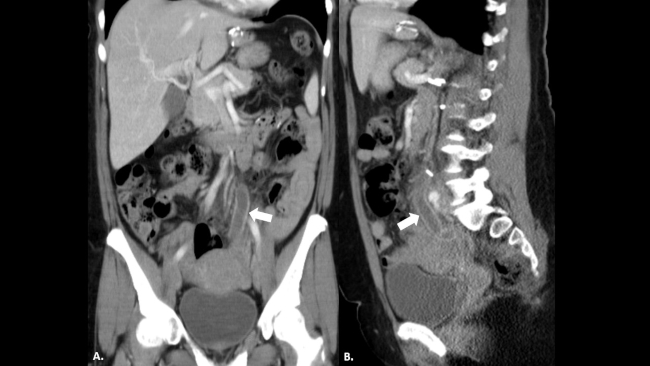

La TC con contraste endovenoso es por amplio margen la mejor técnica para el diagnóstico del EMU. Se trata de un estudio rápido, con alta sensibilidad y especificidad, que nos permite (►Fig. 2) no solo demostrar la existencia de un EMU visible como una estructura tubular dilatada en el trayecto del uréter remanente, con refuerzo y engrosamiento de su pared, sino que también nos ayuda a evaluar las posibles causas del mismo (litiasis, compresión extrínseca de la pared del muñón o tumores) y complicaciones como abscesos asociados en peritoneo o en músculo psoas (►Fig. 3).4,5,6,7,8

Reconstrucciones tomográficas en (a) coronal y (b) sagital del caso descripto en la ►Figura 1. Se reconoce la dilatación del uréter remanente con refuerzo de sus paredes a lo largo de todo su trayecto (flechas blancas).

Paciente trasplantado renal. TC de pelvis con contraste endovenoso (a) en donde se reconoce colección con refuerzo de sus paredes (flecha blanca) adyacente al riñón trasplantado (cabeza de flecha). TC de abdomen del mismo paciente (b), evidenciándose dilatación e inflamación del muñón ureteral izquierdo remanente (flecha negra).

Es importante tener en cuenta que la sensibilidad y especificidad de la TC aumenta en un tomógrafo multislice en relación a un helicoidal, debido al menor espesor de corte y a las reconstrucciones multiplanares. Los hallazgos tomográficos característicos muestran una estructura tubular retroperitoneal dilatada, con refuerzo de sus paredes, en topografía del uréter remanente, con contenido líquido en su interior, en pacientes con el antecedente de nefrectomía homolateral. Una vez realizado el diagnóstico, es necesario evaluar las posibles causas de enfermedad, descartando litiasis, tumor o patología inflamatoria genitourinaria. Desde el punto de vista terapéutico, en la mayoría de los casos se realizará tratamiento antibiótico empírico con posible resolución quirúrgica en un segundo tiempo según su evolución.10,11,12 En algunos casos, se realizará tratamiento intervencionista con un drenaje percutáneo en pacientes con colecciones extraureterales asociadas (►Fig. 6).